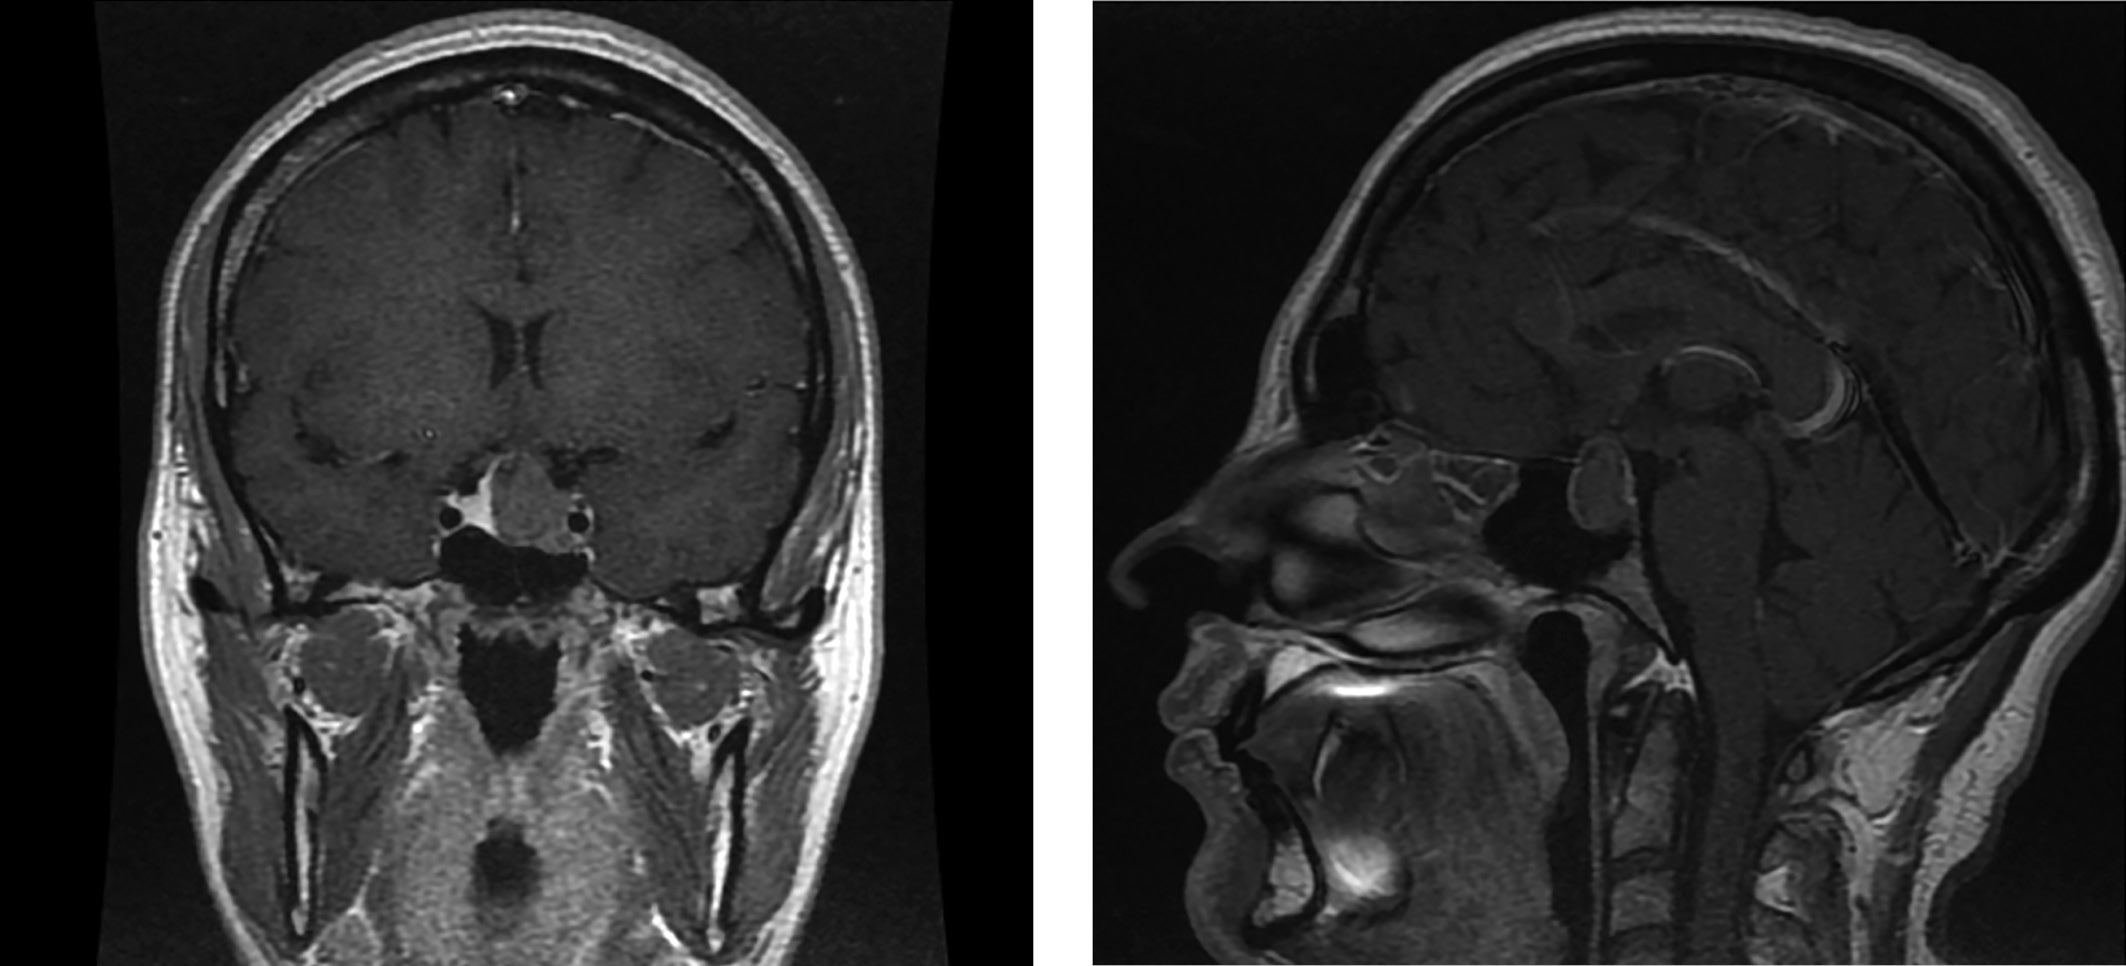

По данным МРТ головного мозга — макроаденома с супра-, пара-, инфраселлярным распространением размерами 17х19х17 мм (рис. 2). Учитывая данные проведенного обследования, характер секреции аденомы был расценен нами как смешанный, характерный для маммосоматотропиномы, и пациентка направлена на хирургическое лечение. Снижение показателя СТГ на 6-е сутки после транссфеноидальной аденомэктомии до 0,599 нг/мл свидетельствовало в пользу ремиссии акромегалии. Также было достигнуто снижение уровня пролактина до 30,8 мЕд/л (64–395).

Рисунок 2. Макроаденома с супра-, пара-, инфраселлярным распространением размерами 17×19×17 мм